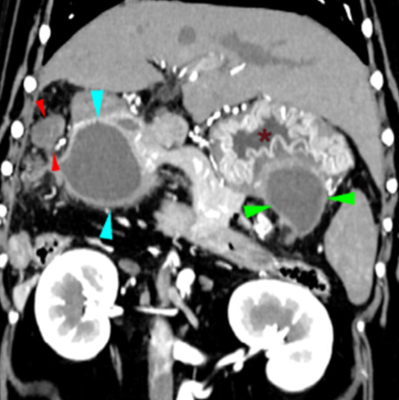

반려견의 위벽내 농양

이번 증례는 위벽에서 발생한 농양 증례이다.

두꺼워졌고, 층간 구조가 잘 안 보이니 종양?이라고 생각하면 안 된다는 의미가 될 것이다.

당연히 FNA를 해보아야 한다.

다발성으로 발생한 게 눈에 띈다.

감별진단에서 꼭 빼지 말고 생각해 보아야 할 것이다.